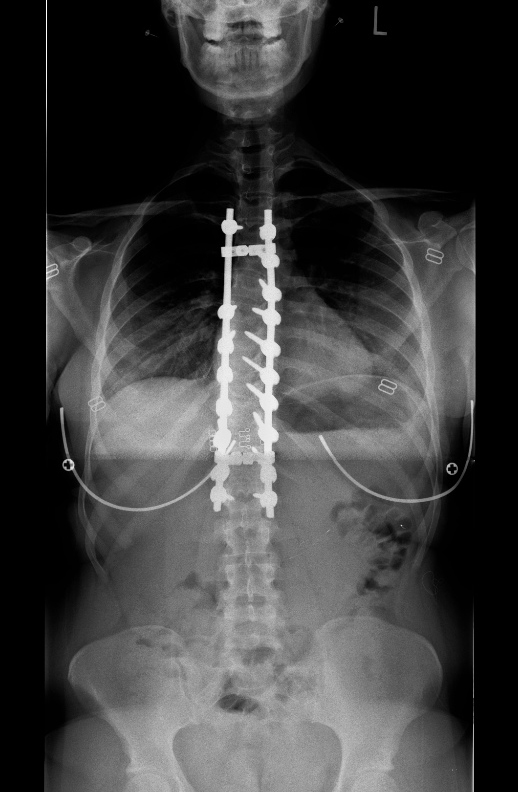

| Pre-op | Post-op |